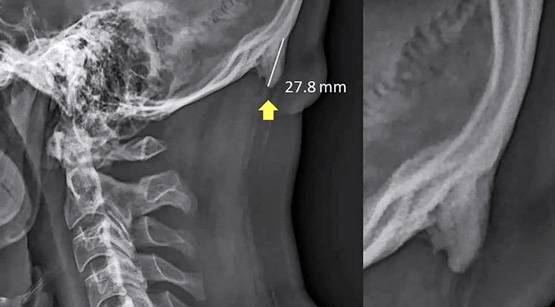

'वॉशिंगटन टाइम्स' की न्यूज रिपोर्ट में उस स्कैन्ड चित्र को भी दिखाया गया है जिसमें खोपड़ी के निचले हिस्से में ये कांटेदार सींगनुमा हड्डी दिख रही है. डॉक्टरों का कहना है कि इंसान की खोपड़ी का वजन करीब साढ़े चार किलो होता है.

ऑस्ट्रेलिया के क्‍वींसलैंड स्थित सनशाइन कोस्ट यूनिवर्सिटी में हुई इस रिसर्च में इसे विस्तृत तरीके से समझाया गया है. इसमें कहा गया है कि  रीढ़ की हड्डी से शरीर का वजन शिफ्ट होकर सिर के पीछे की मांसपेशियों तक जाता है. इससे कनेक्टिंग टेंडन और लिगामेंट्स में हड्डी विकसित होती है. इसी का रिजल्ट है कि युवाओं में हुक या सींग की तरह की हड्डियां बढ़ रही हैं, जो गर्दन के ठीक ऊपर की तरह खोपड़ी से बाहर निकली हुई है.

डॉक्टरों ने रिसर्च में पाया कि मोबाइल चलाते वक्त लोग अपने सिर को  आगे पीछे की तरफ हिलाया करते हैं. ऐसे में गर्दन के निचले हिस्से की मांसपेशियों में खिंचाव आने लगता है. यही वजह है कि कुछ दिनों बाद इसी कारण हड्डियां बाहर की तरफ निकल जाती हैं. सिर पर ज्यादा दबाव पड़ने के चलत ये सींग जैसी दिखने वाली हड्डियां निकल रही हैं.